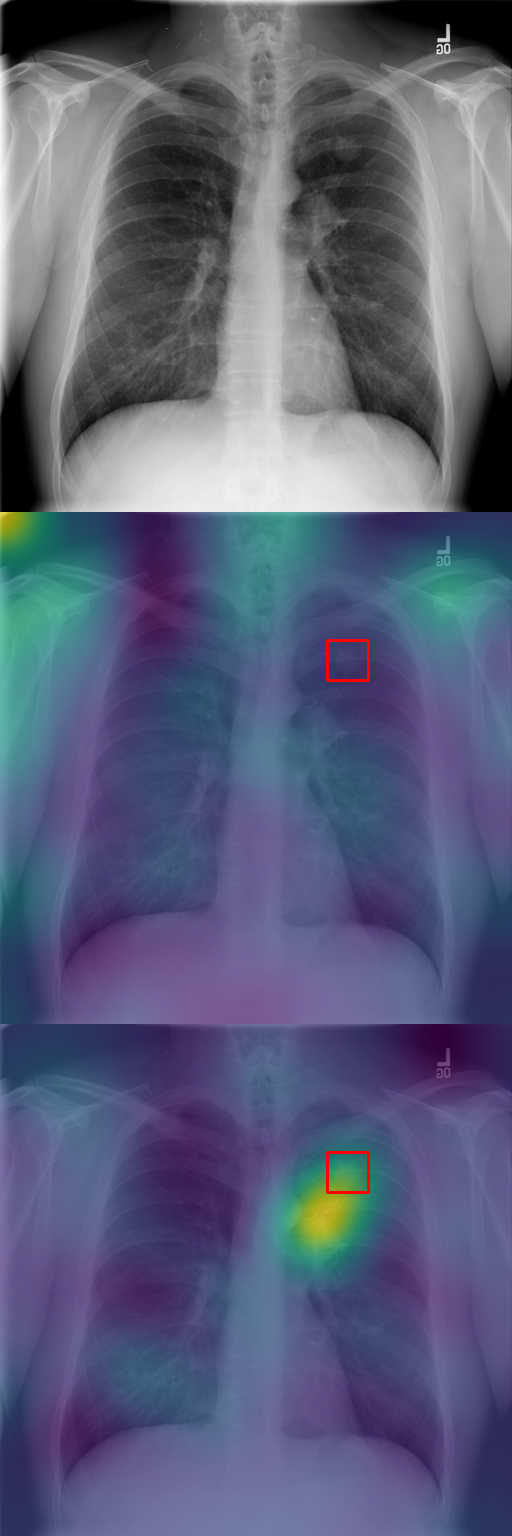

In Section 4.2, we discussed how typicality helps find relevant patches for an input label. In this section, we test this idea on completely different images: X-rays of patients who may suffer from a combination of various thorax diseases. We finetune Stable Diffusion on the ChestX-ray8 dataset [46] containing 108,948 frontal-view X-ray images annotated with 14 single-word disease-name labels. Experts annotated a test set of 879 images with 7 diseases with rectangular regions of interest (ROI) for each disease. For each image, we compute typicality per latent feature, interpolate the resulting typicality to the input dimension, and blur the resulting typicality map for visualization. In Fig. 11, we show the resulting typicality maps together with the ROI annotation before and after finetuning. Finetuning clearly improves the localization. We quantify this effect by computing the area under the precision recall-curve [5] (AUC-PR) associated with the ROIs. As reported in Fig. 11, we see consistent improvement of this measure when finetuning the network (from 3.2% to 9.6%), ranging from +3.5% for Pneumonothorax (from 3% to 6%) to +14.6% for Mass (from 2% to 16.6%), which are respectively the least and most localized diseases. Similar to our other experiments, finetuning uses only image labels without localization supervision.